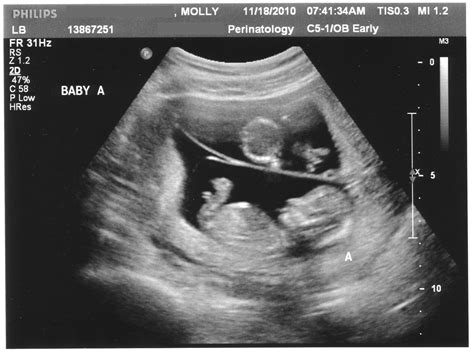

Timing is critical for this specific ultrasound. Because the fluid at the back of the neck can be reabsorbed by the baby's developing lymphatic system, the window for performing this scan is narrow. Most practitioners conduct the Nuchal Translucency Screening between 11 weeks and 13 weeks plus 6 days of gestation. If the scan is performed too early or too late, the results may not be accurate.

During the appointment, a sonographer will use an ultrasound transducer on your abdomen or, less commonly, transvaginally, to obtain a clear image of the fetus. The process is generally quick, painless, and completely safe for both the parent and the baby. The sonographer carefully measures the thickness of the fluid collection at the nape of the neck while the baby is lying in a neutral position.

💡 Note: The accuracy of the Nuchal Translucency measurement relies heavily on the baby's position; if the baby is curled up or moving too much, the technician may need a little extra time to get the perfect angle.